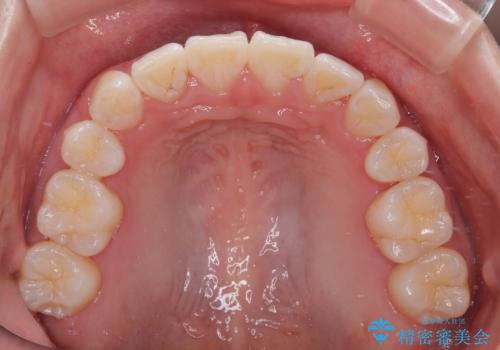

わずか2年弱で一気に口元が変化し、患者様には大変満足していただけました。

- 前歯がくちばしのように飛び出していることを気にして来院された患者様です。

唇が前方に突出している横顔が気になっているため、上下左右の第一小臼歯4本を抜歯し、ワイヤー装置にて矯正治療を行うこととしました。